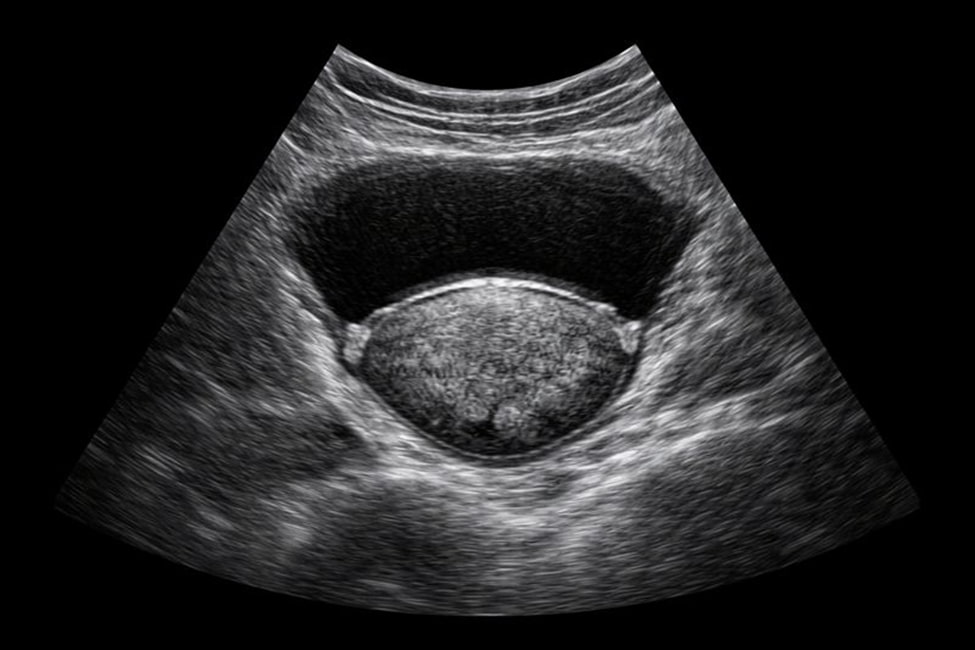

УЗИ предстательной железы трансабдоминально — это ультразвуковой метод визуализации, при котором сканирование выполняется через брюшной отдел. Исследование производится через переднюю поверхность тела, что делает процедуру максимально комфортной и психологически простой для пациента.

Во время обследования ультразвуковой датчик устанавливается на живот. Наполненный мочевой пузырь служит естественным акустическим окном. Врач получает четкое изображение органа, его контуров и прилегающих структур. Данный способ нередко используется как альтернатива трансректальной диагностике, когда последняя временно не рекомендована или противопоказана.

Трансабдоминальное УЗИ простаты позволяет получить информацию об анатомических характеристиках органа и окружающих тканей. Врач оценивает размер, форму, четкость контуров и структуру предстательной железы.

Кроме того, метод дает возможность выявлять косвенные признаки воспалительных процессов, доброкачественных изменений и иных состояний мочеполовой системы. Дополнительно анализируется стенка мочевого пузыря и ее взаимосвязь с предстательной железой, что повышает диагностическую ценность исследования.